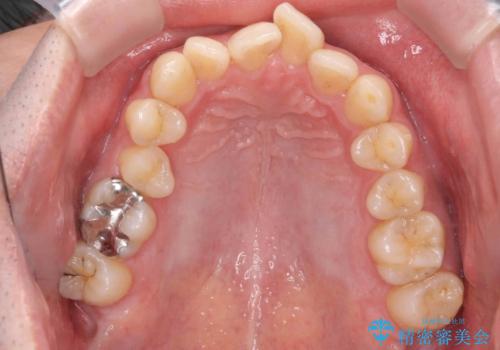

- 矯正装置

- インビザライン

奥歯のかみ合わせを特に変えず、前歯の並びを整える治療をおこないました。

奥歯のかみ合わせは1本分ずれているとはいえ、1歯対2歯の交互のかみ合わせになっているため、そのままにしてもそこまで大きなデメリットはありません。

今回は右のかみ合わせはそのままにしました。左は特に初めから問題ない状態でした。

右のかみ合わせを変えず部分矯正にしたことによって、治療が短期間で済み、また、ワイヤーでなくインビザラインで治療が可能、歯も抜かなくて済むなどメリットの多い方法であるといえます。